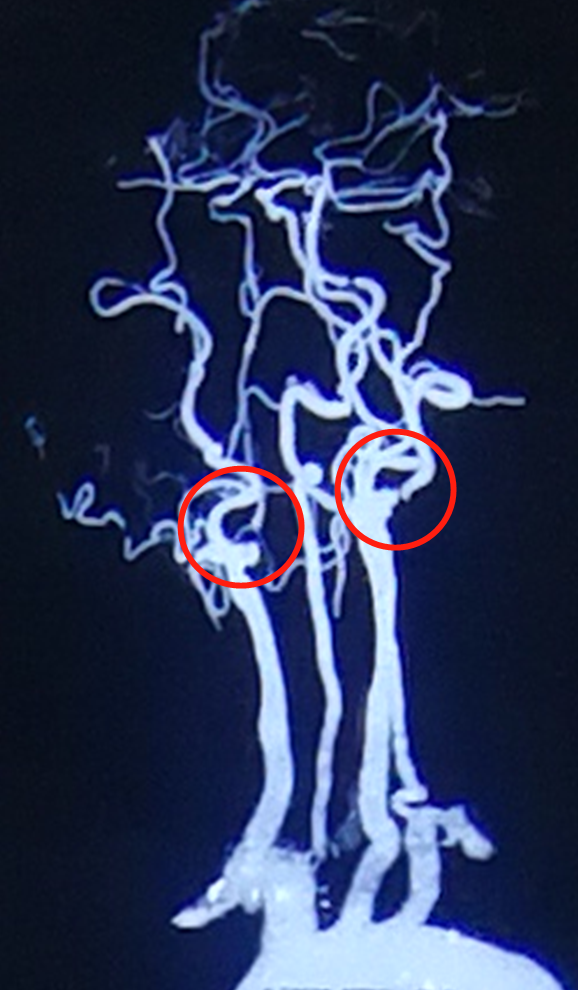

入院给予对症抗凝、扩血管等治疗后好转,右侧肢体肌力恢复,语言恢复,住院期间进行头部CTA检查:右侧颈动脉血管官腔慢性闭塞,远端血管逆行显影,左侧颈动脉内动脉重度狭窄。

? 左侧颈内动脉狭窄(重度,90%以上狭窄)

? 右侧颈动脉闭塞

张先生两侧颈动脉都狭窄。幸亏他及时就医,并听从医嘱,进行颈动脉内膜剥脱术,从而将左侧颈动脉的斑块清除干净(由于本次症状在右侧肢体,所以先对其左侧颈动脉进行手术,待到春节后,再对右侧颈动脉进行手术);否则(不做手术,对病情置之不理),左侧颈动脉就真的会闭塞了。

手术过程中,由于张先生左侧颈动脉中有大量斑阻塞血管,并且血管迂曲,所以进行翻转式颈动脉内膜剥脱手术,即:取出斑块,将弯曲的血管下移(1厘米)、拉直、缝合。